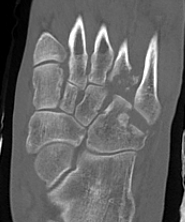

CT

cubcubcub